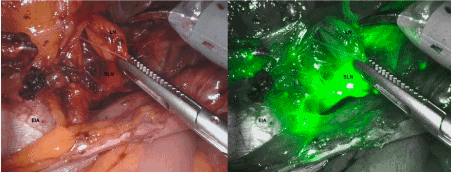

The figures 2 and 3 show the left side SLN in normal view (left) and by NIR fluorescent system (right). In upper part of the figure it is observed another lymph node (LN) of the same lymphatic chain with a clearly lower fluorescence. Both are located adjacent to the Extern Iliac Artery (EIA). In the figure 4, we can see the left SLN after its complete dissection (Figures 2-4).

Figure 2. The left side SLN in normal view (left) and by NIR fluorescent system (right).

Figure 3. The left side SLN in normal view (left) and by NIR fluorescent system (right).